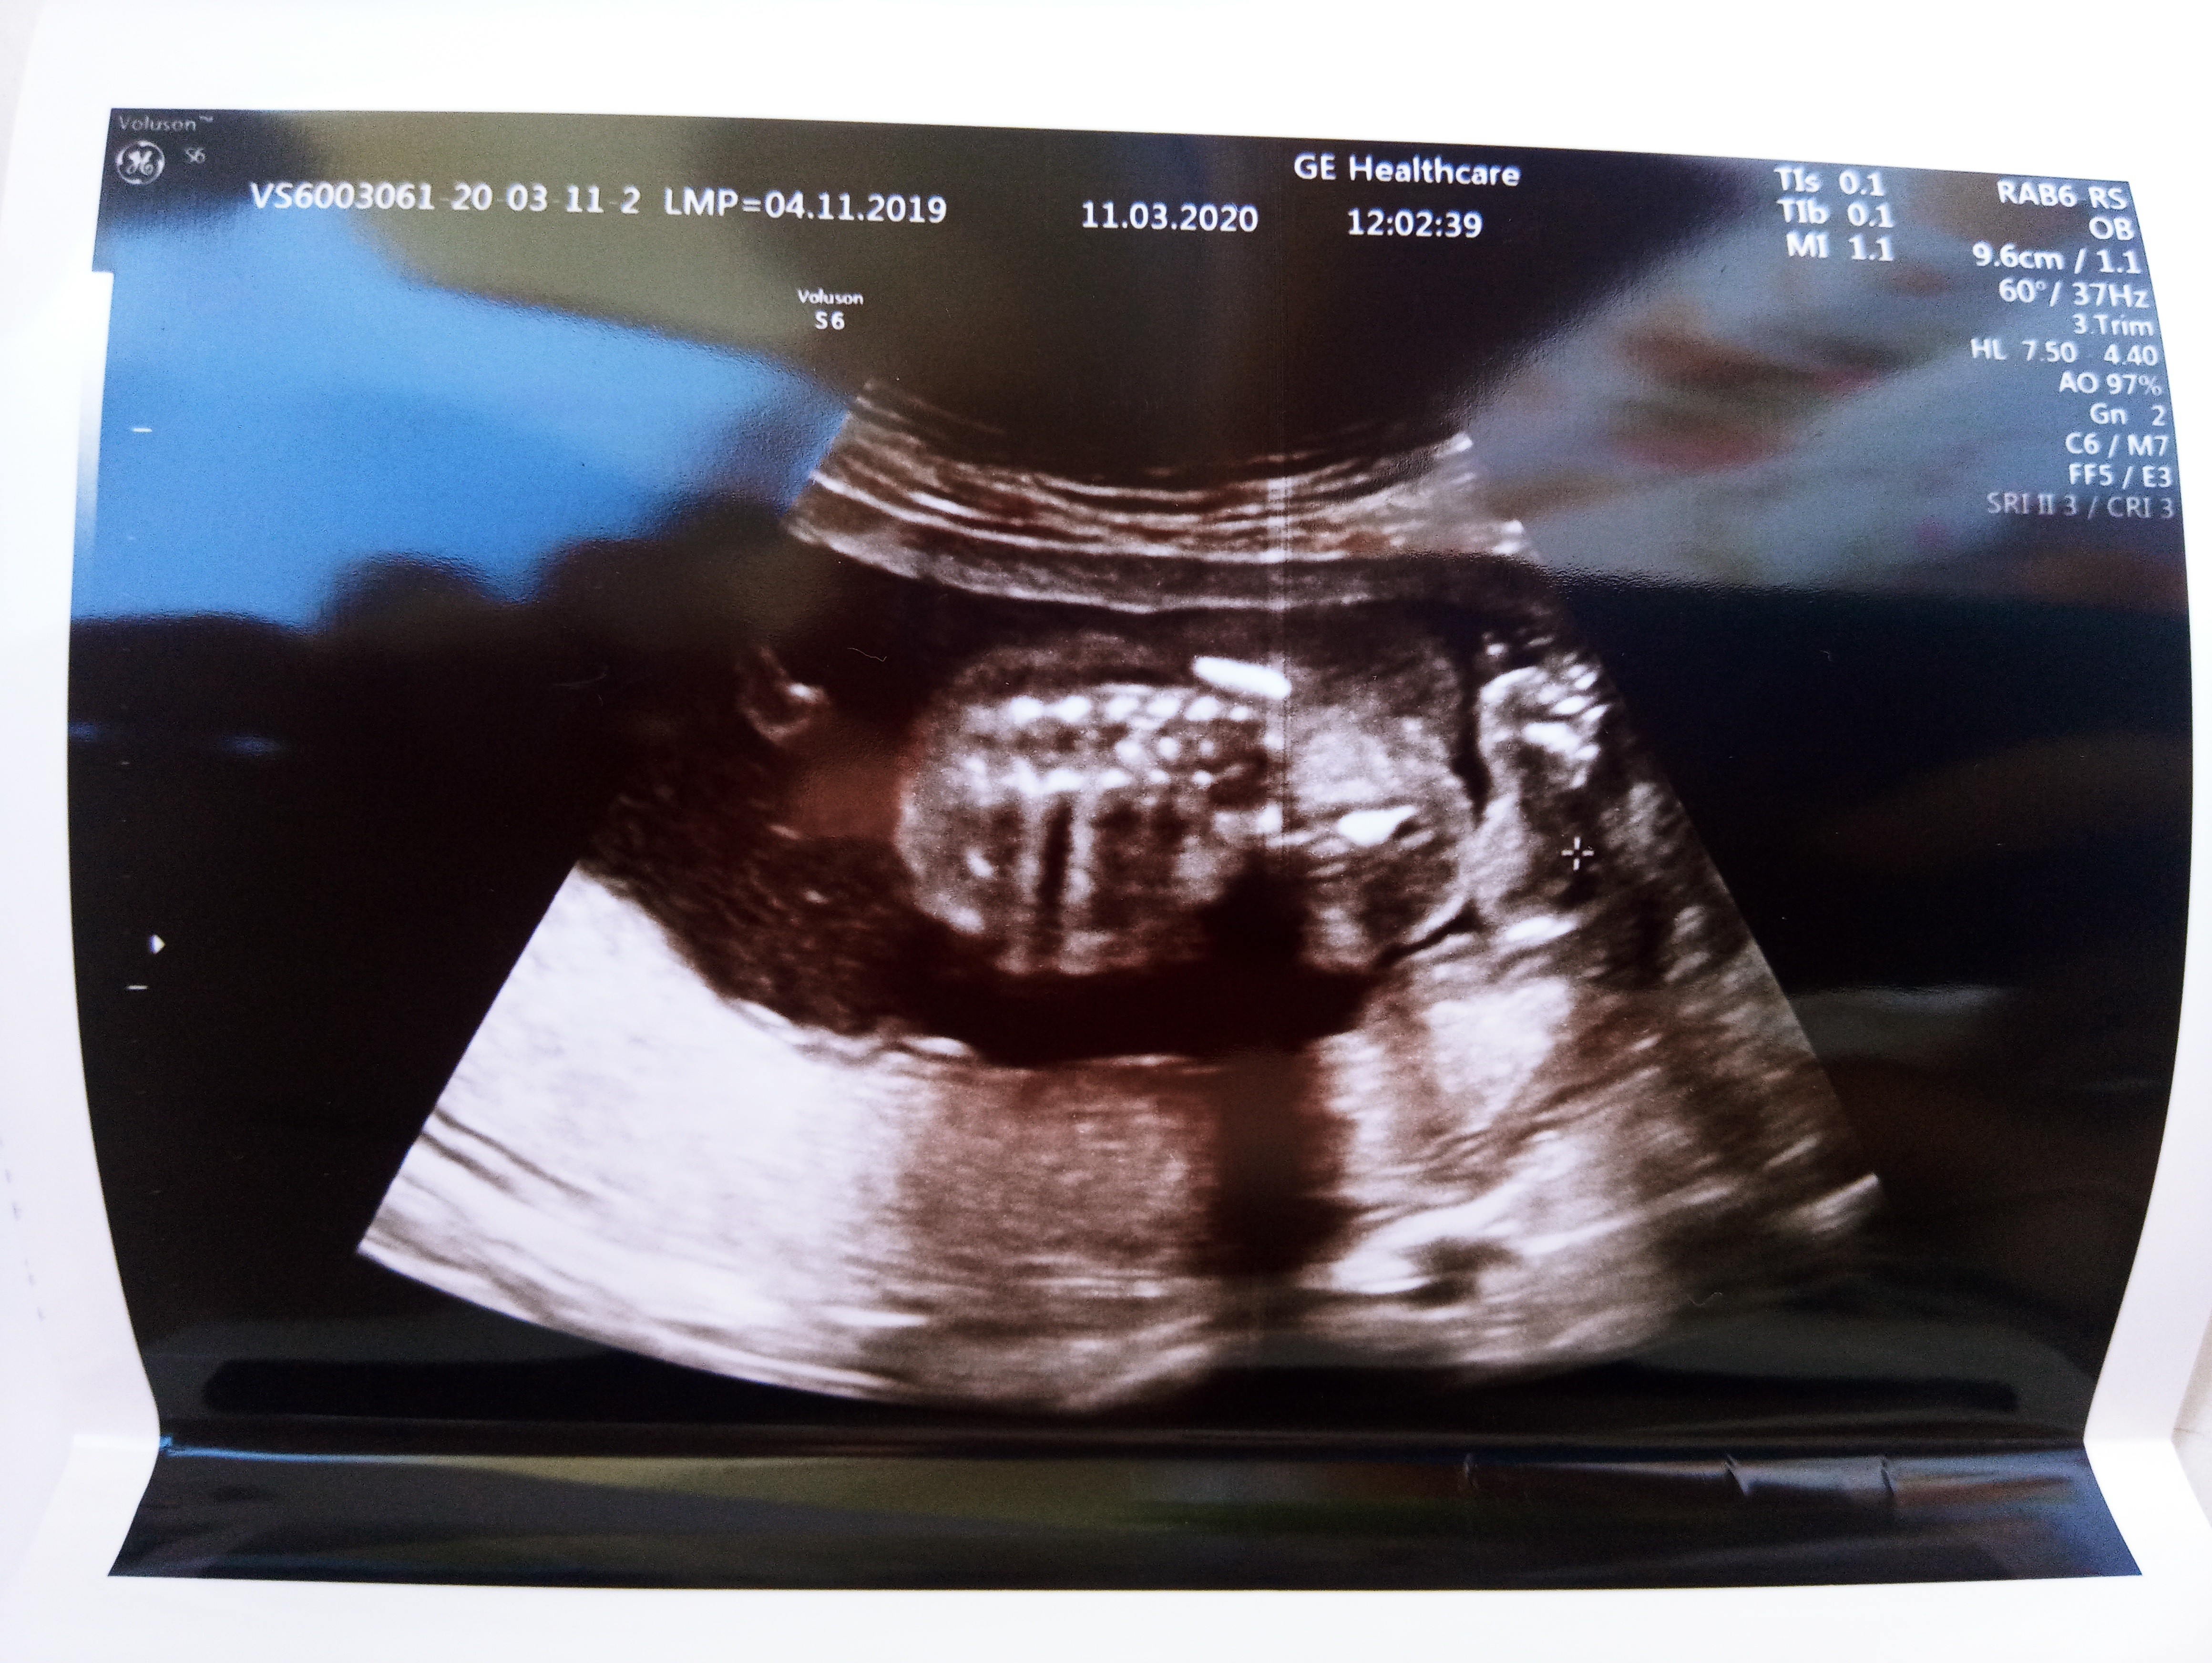

A ja jestem właśnie po długieeeej wizycie. Będzie na 100% dziewczynkażadnego siusiaka nigdzie nie ma.

Mój też miał duże stopy jak się urodziłA nie chciała pokazać co ma między nogami ale później się udało i prezentowała odważnie. Ma bardzo duże stopymierzy 23 cm i waży 260g. Jestesmy tacy szczęśliwi. Bylismy w gabinecie razem z młodszym synem i dla niego to był mega szok. Teraz wracamy i ciągle wymyśla imiona

A tutaj foteczka.. stópka taka wielka, że ja nie wiem jak to będzie.. ahaha